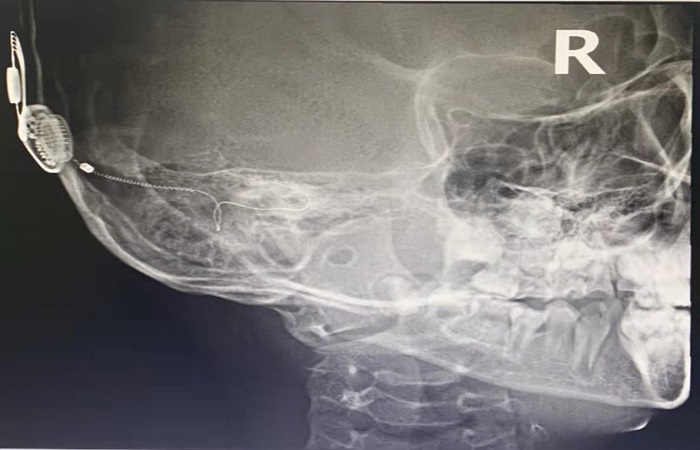

術(shù)后為軒軒行頭顱X片,見(jiàn)人工耳蝸電極漂亮地循著耳蝸的“軌跡”繞圈,表示著人工耳蝸電極成功植入。